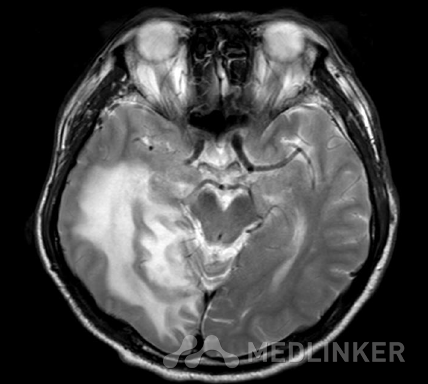

MR:1、双侧额、顶叶、右侧颞叶、枕叶、左侧颞叶岛盖皮层、皮层下区多发异常信号结节,环状或结节状强化,周围见环状、斑片状、指状水肿区,拟多发脑转移瘤。 2、双侧额顶叶皮层下区、右侧基底节、尾状核区、胼胝体区多发腔隙性缺血、部分梗塞、软化灶。 3、两侧筛窦粘膜增厚。鼻中隔稍左偏,两侧下鼻甲肥厚。